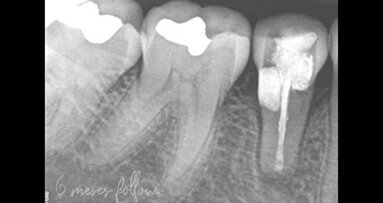

1. Le lastre sono state svolte per ogni paziente all’inizio dello studio (radiografia prefrenulotomia) e dopo 6 mesi, cioè subito dopo l’esecuzione dell’intervento (radiografia postfrenulotomia).